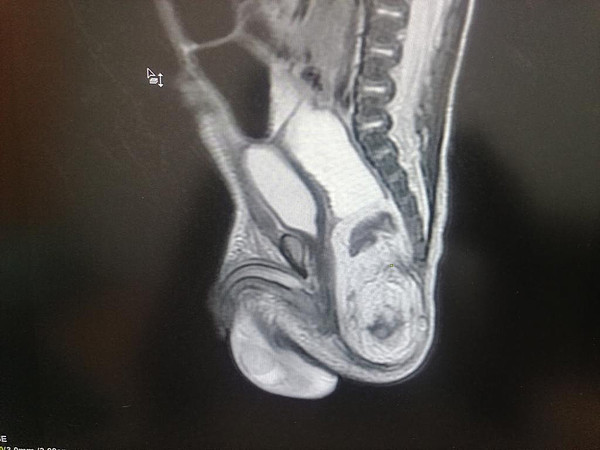

IMG-20221223-WA0030.